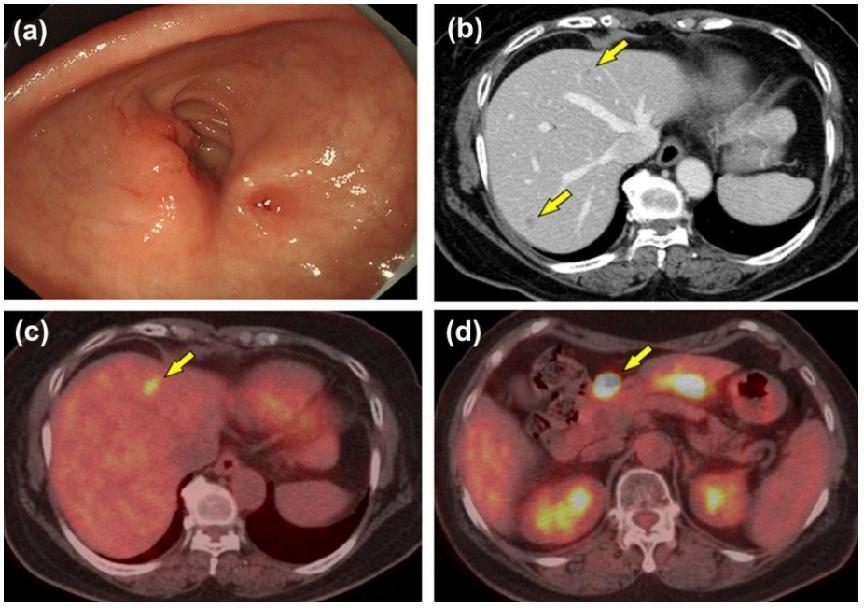

患者接受一线治疗10个月后,CT和FDG-PET检查发现原发病灶明显缩小(图5a),仅残留3个肝转移灶(图5b,c),区域淋巴结肿大(图5d)。复查CEA再次升高(图3)。

图5:一线治疗10个月后内镜和影像学检查(a,EGD;b,增强CT;c,FDG-PET;d,淋巴结肿大)